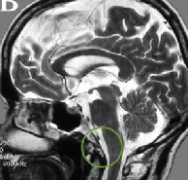

枕骨大孔区脑膜瘤案例。多年颈痛,竟是脑膜瘤在作怪德国一位57岁的女士,多年以来,一直饱受颈痛的折磨,近来,还出现了走路乏力,腿不听使唤且步...

大孔脑膜脑膜瘤 (FMM)占全部颅内脑膜瘤的1.8-4%,约占颅后颅窝脑膜瘤的6.5%。尽管显微外科和颅底技术不断发展,但枕骨大孔区脑膜瘤(FMM)的外科治...

枕骨大孔区的 脑肿瘤 长期以来一直是外科医生的难题,他们不仅面临诊断困难,还面临危险肿瘤切除的技术障碍。历史上,手术往往以呼吸衰竭和死亡告...